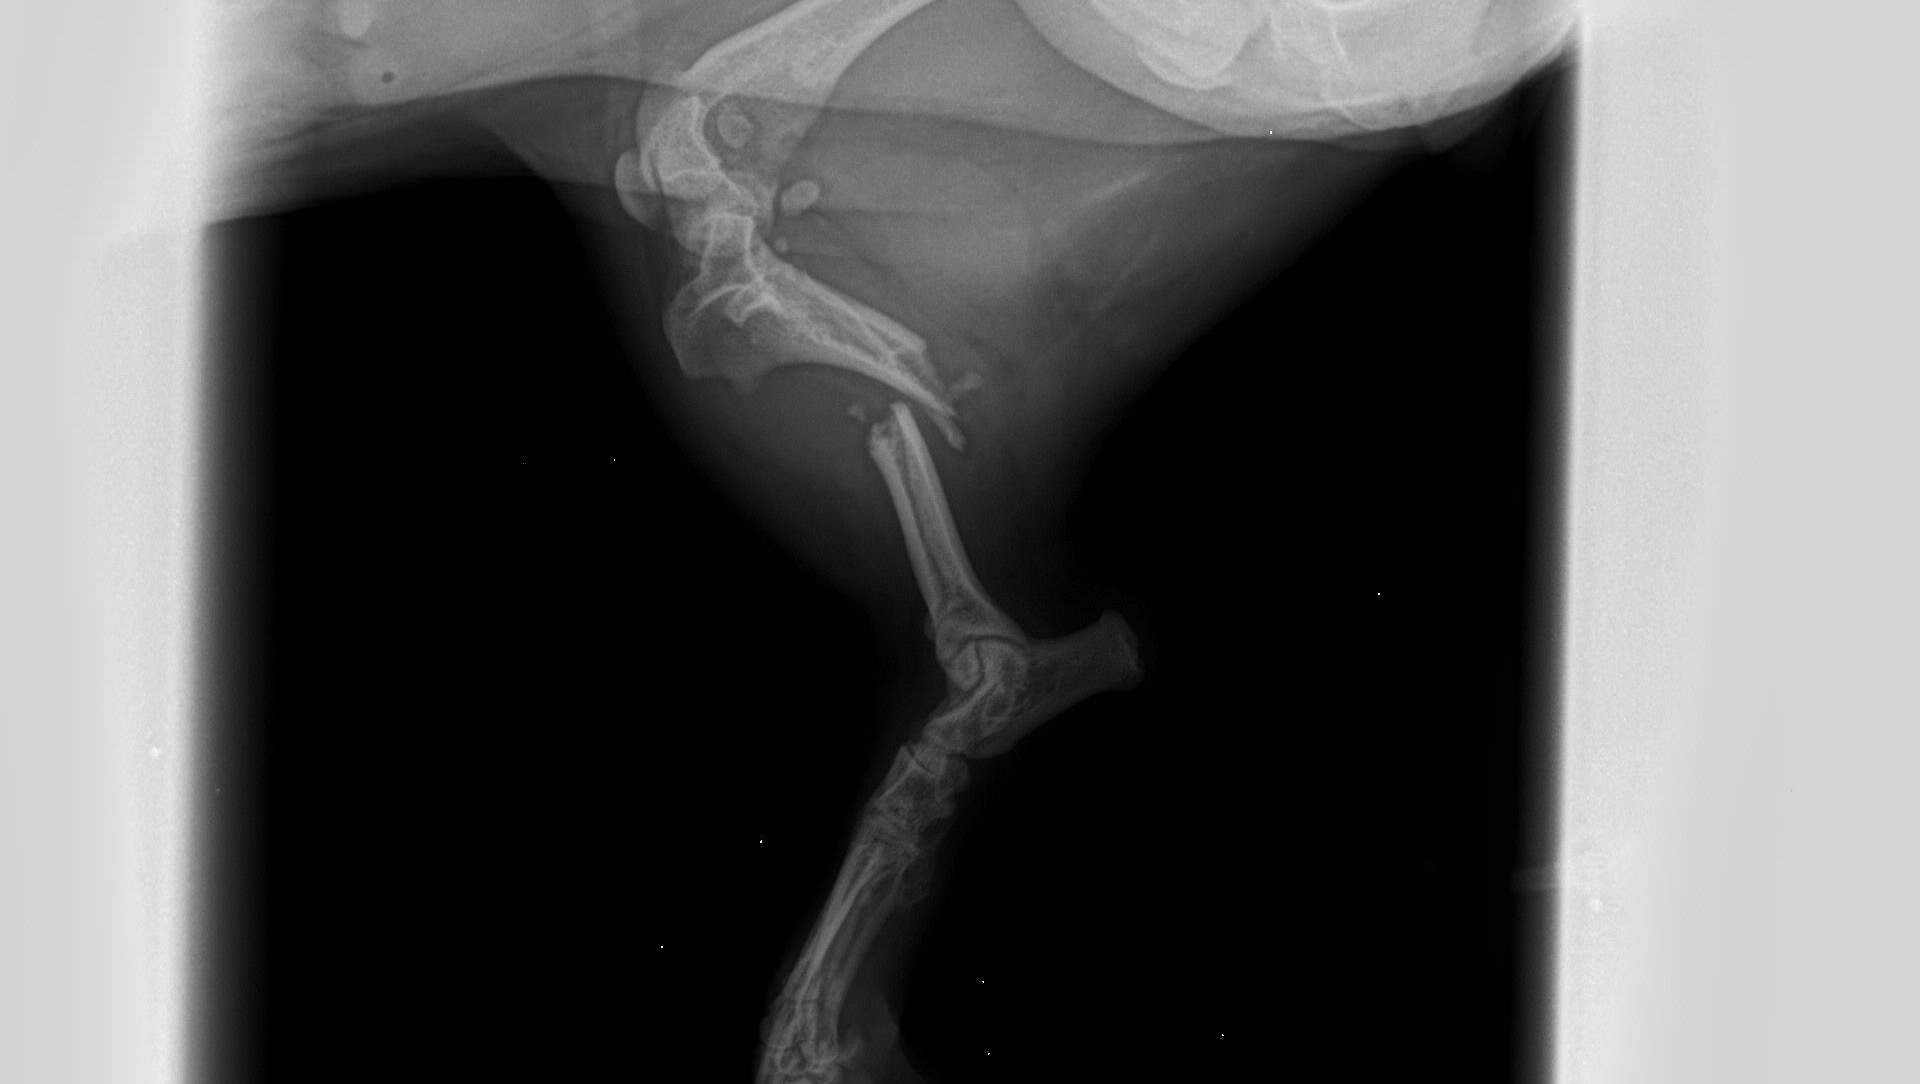

The dogs name is unknown, but we had to give her a name so we decided on Tulip temporarily. Tulip was taken to the veterinarian and we discovered she has a broken back leg and a small fracture in her hip. She will need surgery with external fixators to repair the leg. Her bloodwork is normal, she was checked for intestinal parasites and heart worms which were both negative. She does have some bruising on her leg and her back from debris falling on her but otherwise she is in good spirits.

She currently has a splint on her leg and is on pain medication until she can be seen by the surgeon on January 19th.